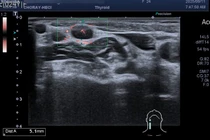

Ung thư tuyến giáp là loại ung thư có tỷ lệ mắc cao nhất ở nữ giới đến khám, vượt trên các bệnh lý ung thư thường gặp khác như vú, phổi, đại tràng và dạ dày.

Ung thư tuyến giáp thể nhú phát hiện trễ và để kéo dài sẽ khiến khối u diễn tiến di căn xa, ngoài phẫu thuật cắt tuyến giáp, nạo hạch sẽ phải hóa, xạ trị.